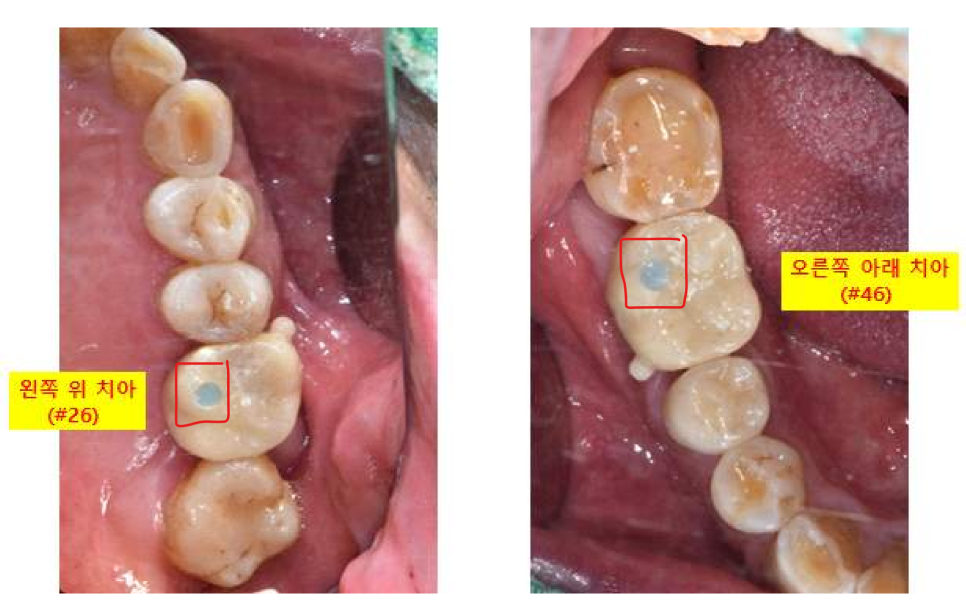

파노라마 엑스레이 상에서 좋지 않게 보이는

오른쪽 아래 어금니도 같이 설명드렸습니다.

오른쪽 아래 어금니 같은 경우는

그냥 눈으로 봤을 때는 크라운 보철이 되어 있기 때문에

상태가 너무 좋아 보이지만

엑스레이상으로 보면 뿌리에 길게 신경치료 한 부분이 보이고

"뿌리 끝 염증으로 주변 뼈가 까맣게 녹고 있는 모습"이 보입니다.

환자분은 현재 왼쪽 위 어금니 통증 때문에

오른쪽 아래는 통증은 크지 않다고 하셨지만

염증은 한번 생기면 사라지지 않고, 계속 뼈를 녹입니다.

일단 오른쪽 아래 큰어금니 염증이 크고

뿌리 부분 뼈를 많이 녹여놓았기 때문에

오른쪽 아래 큰 어금니는 더 이상 뼈를 손상시키기 전에

임플란트를 진행하기로 하 였습니다.

<치료 결정>

왼쪽 위 큰어금니 (26번치아) : 임플란트

오른쪽 아래 큰어금니 (46번치아) : 발치 + 임플란트 + 뼈이식

본 뜨는 작업을 진행할 때는

임플란트위에 잠겨져 있던 뚜껑나사를

스캔하는 장치(스캔바디)로 바꾸어서 3D 스캔을 진행 한 다음

다시 원래대로 입안에 있던 뚜껑나사로 연결 해드립니다.

이 테스트 기간에 볼 쪽에 둥근 손잡이를 달아놓는데요,

완전히 붙일 때 보철을 잡고 뺄 수 있도록 만든 손잡이입니다.

완전히 붙일 때는 깔끔하게 제거해 드리니 걱정하지 마세요~^^

파란색으로 보이는 부분은 조이는 나사가

임플란트로 들어가는 통로입니다

이 통로는 혹시라도 나중에

식사하시다가 보철이 깨지거나

나사가 풀리는 등의 문제가 생길 경우에

(자주 발생하지 않으니 너무 걱정 마세요~)

임플란트 전체를 제거하지 않고

보철만 제거할 수 있도록 만들어놓은 통로입니다.

통로에 있는 파란색재료는,

역시나 마무리할 때 치아색으로 다 메워 드립니다! 걱정하지 마세요!